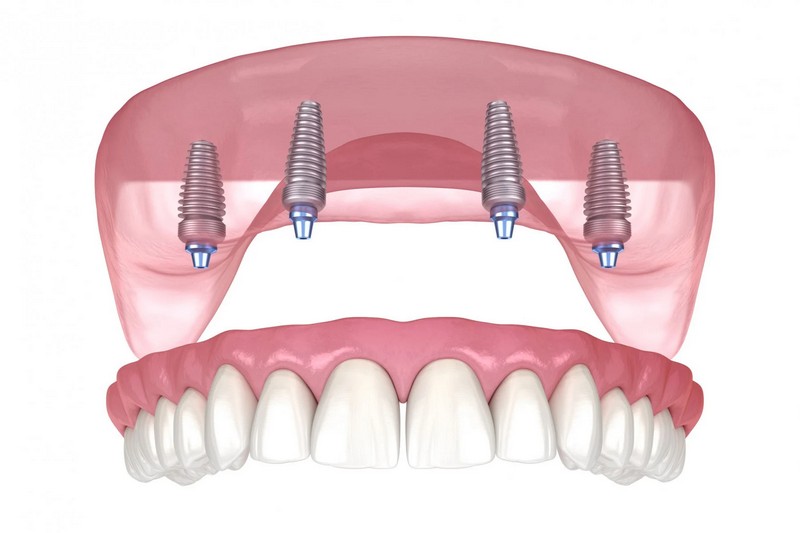

All on 4 / All on X